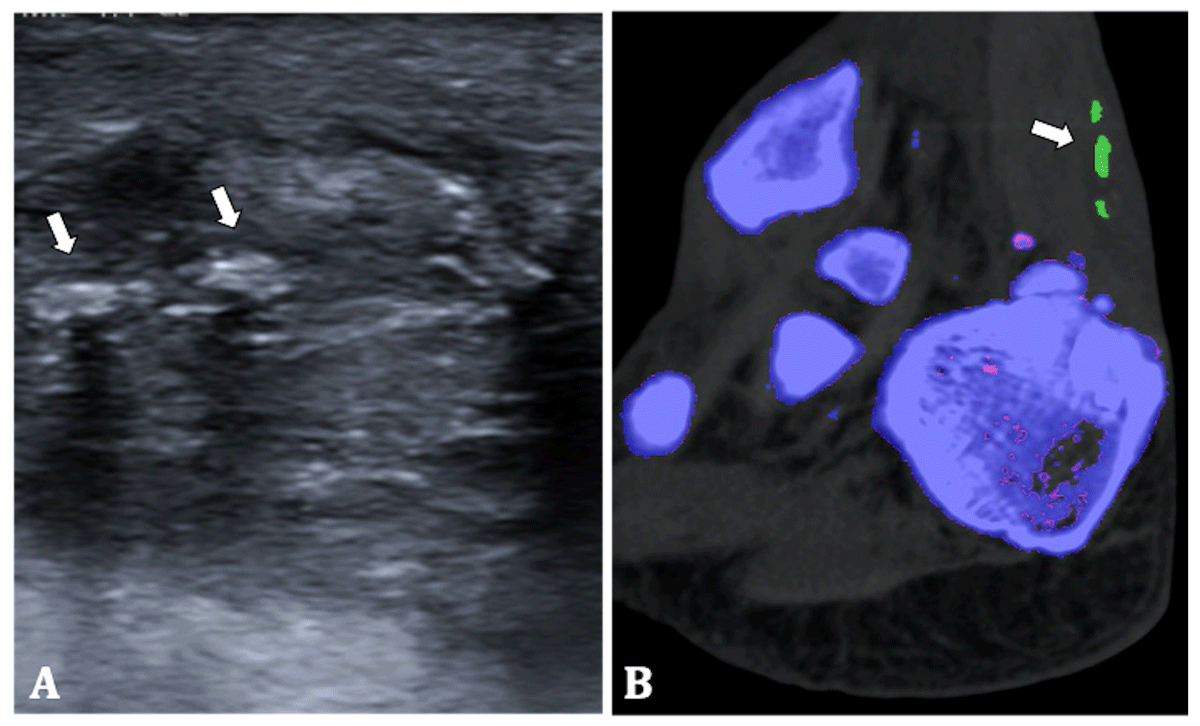

Ultrasound (US) of the tendon showed signs of inflammation and multiple hyperechoic nodules (Figure 4). To differentiate between tendinous calcifications or MSU crystal depositions DECT was performed. The same setup as in the previous cases was used. Colour-coded DECT images showed the presence of MSU crystals in the right Achilles tendon (Figure 4). Therefore, the patient was diagnosed with oligoarticular gout with tendinous involvement.

Figure 4

70-year-old man. (A) Ultrasound of the right Achilles tendon shows tendon thickening and multiple hyperechoic nodules (arrows). (B) Colour-coded DECT image shows MSU crystal deposition in the Achilles tendon (arrow).